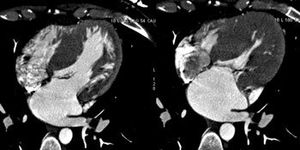

Experts present a case of recurrent small cell lung cancer presenting with a cutaneous metastatic nodule in the right breast.